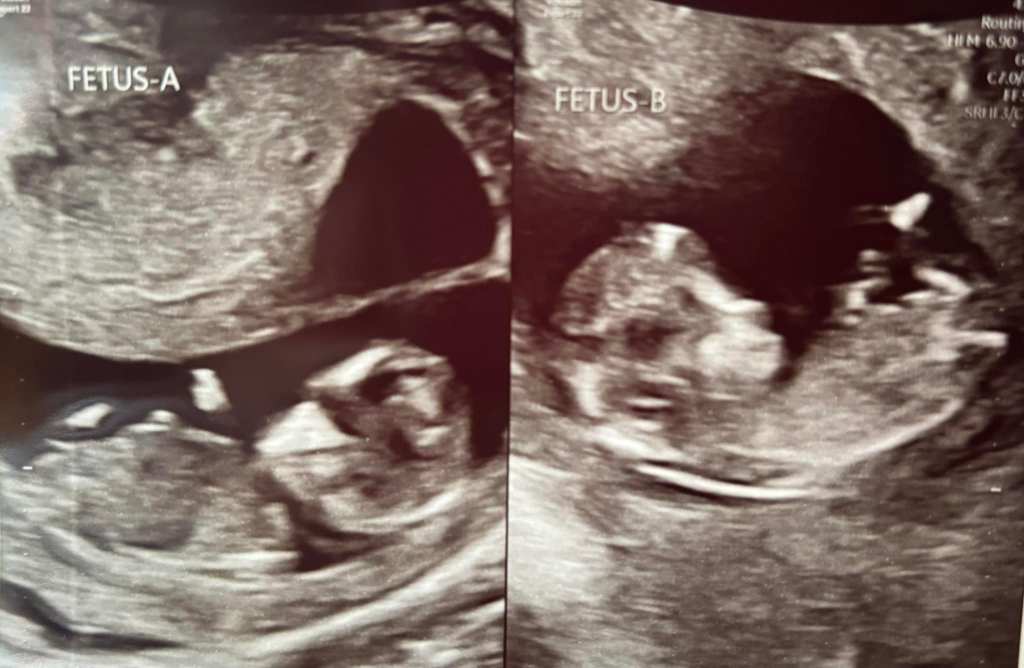

So! went in for my first sonogram and went… oh! Twins! Okay then… Went from “You’ll never be able to get pregnant” (being told that the last 15 years) right to “Oh, you’re having twins!”

My house is about to become a lot more pink! Besides my small dog, all the people and animals in my house are boys. I’m severely outnumbered. Well, not any more! Lilliana & Layla will be joining our house around September! I have a registry started as well as some things we already owned that were either girl stuff from friends, or “gender neutral” (boy stuff that girls can totally wear). I even have my baby clothes that are so freaking cute and I can’t wait to dress the girls up! I’m gonna have them so girly while I can LOL.